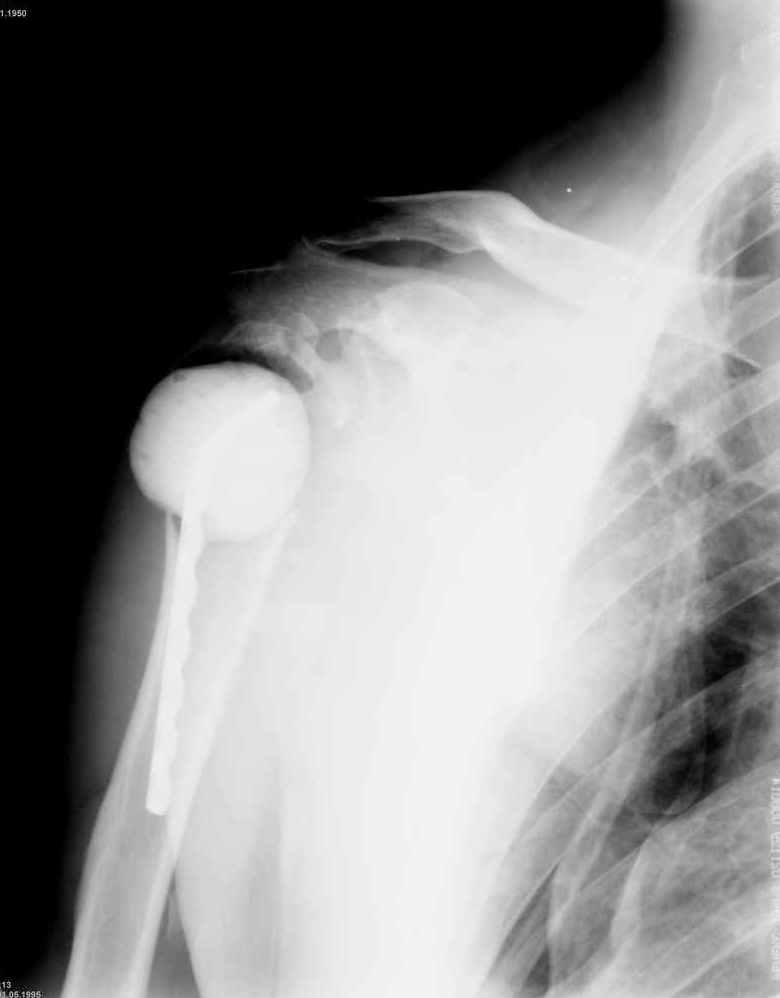

Уважаемые коллеги. Недавно из нашего отделения был выписан пациент 54 лет с закрытым переломом плечевой кости. Из анамнеза: за 2 дня до поступления в НИИСП, в состоянии алкогольного опьянения упал с лестницы на даче (высота 3-4 метра) с упором на правую руку. Через двое суток обратился за медицинской помощью. Доставлен бригадой "Скорой помощи".Правый плечевой сустав умеренно деформирован. По внутренней поверхности плеча имеется кровоподтек. При пальпации плечевого сустава имеется умеренная болезненность. Активные и пассивные движения болезненные. Снижена чувствительность по тыльной поверхности пальцев кисти и отсутствует активное разгибание кисти и пальцев. Имеется подкожная эмфизема шеи, верхней половины грудной клетки (рис 1, 2). На рентгенограмме: оскольчатый перелом головки плечевой кости со значительным смещением, перелом 2-3 ребер справа, тканевая эмфизема (рис 3). КТ при поступлении: перелом головки плечевой кости в области анатомической шейки со смещением отломка головки в грудную полость, правосторонний гидроторакс, перелом 2-3-4 ребер справа. (рис 4). Через двое суток после поступления выполнена операция: атипичная торакотомия, эвакуация свернувшегося гемоторакса, удаление инородного тела (головки плечевой кости) из плевральной полости (при этом выявлено имеющееся повреждение париетального и висцерального листков плевры) (рис. 5), дренирование плевральной полости, замещение проксимального конца плечевой кости спейсером из костного цемента с антибиотиком (рис. 6). Послеоперационный период протекал гладко. При контрольной рентгенографии положение спейсера удовлетворительное (рис. 7, 8). Дренаж из плевральной полости удален через 3 суток после вмешательства. Послеоперационная рана зажила первичным натяжением. Через 12 дней после операции больной выписан на амбулаторное лечение.

После операции мы не исключали развитие пневмоторакса, плеврита, гемоторакса или эмпиемы плевры. Поэтому мы посчитали возможным заместить дефект плечевой кости спейсером с антибиотиком, а эндопротезирование выполнить в «чистых» условиях.

Александр, спасибо за столь высокую оценку. Нисколько не сомневаюсь, что и нам есть чему у Вас поучиться. Для иллюстрации прилагаю сегодняшний снимок с нашего обхода в шоковом зале реанимации (рис. 2).